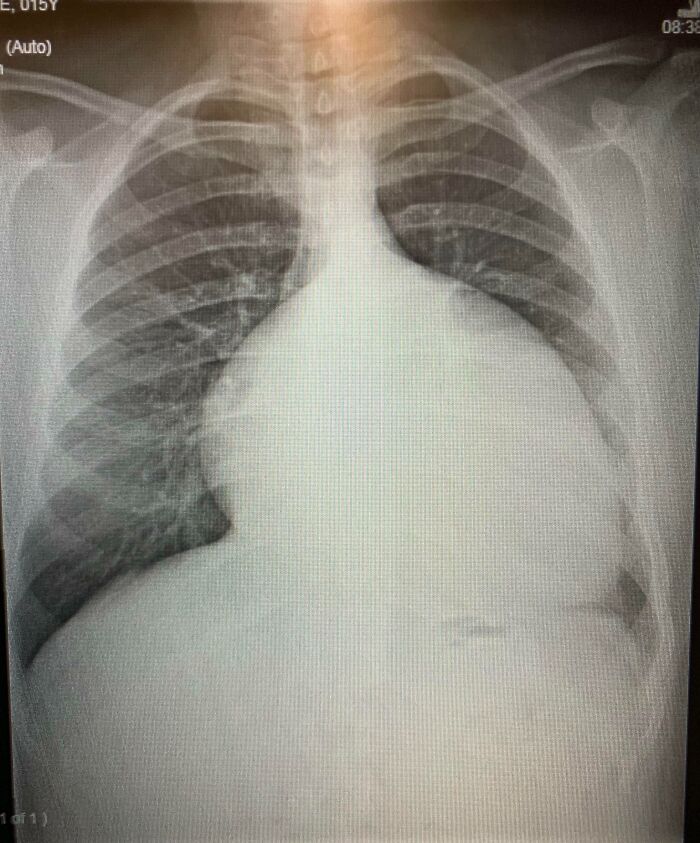

Mi corazón agrandado a los 15 años (2012) antes de las cirugías